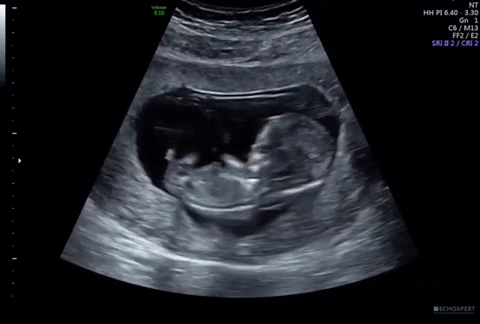

프로젝트 화면으로 아기의 옆모습이 보였다. 어디가 코인지, 턱인지 제법 구분도 잘 되는 데다 몸속에서 빠른 속도로 뛰는 심장도 선명하게 볼 수 있었다. 아, 좋은 초음파 기계라는 게 이런 거였구나. 그전까지 언제나 조금씩 흐릿하게 보여서 온갖 상상력과 공간지각력을 동원했어야 했던 지난 초음파 검진들이 순식간에 지나갔다.

그리고 초음파 선생님은 이곳저곳을 비춰가면서 심장이 잘 뛰고 있는지, 팔다리, 손발은 다 잘 발달하고 있는지, 뇌는 예쁘게 만들어지고 있는지, 탯줄과 태반은 잘 자리를 잡았는지 등을 약 20분간 꼼꼼하게 검사했다.

그리고 조금 남은 시간 동안 초음파로 아이의 모습을 이리저리 볼 수 있었다.

너무 선명히 보이는 아기의 손과 손가락에 그 어느 영화나 드라마보다 몰입했다. 그 기분은 마치 맨 눈으로 그 작은 방 시계의 초침을 바라볼 때와 같았다. 아니, 실은 그 강도는 그에 비할 바가 못 되었다. 아주 강렬한 경험이었다. 나는 한눈에 마음을 뺏기고, 급기야 사랑에 빠져 버렸다.